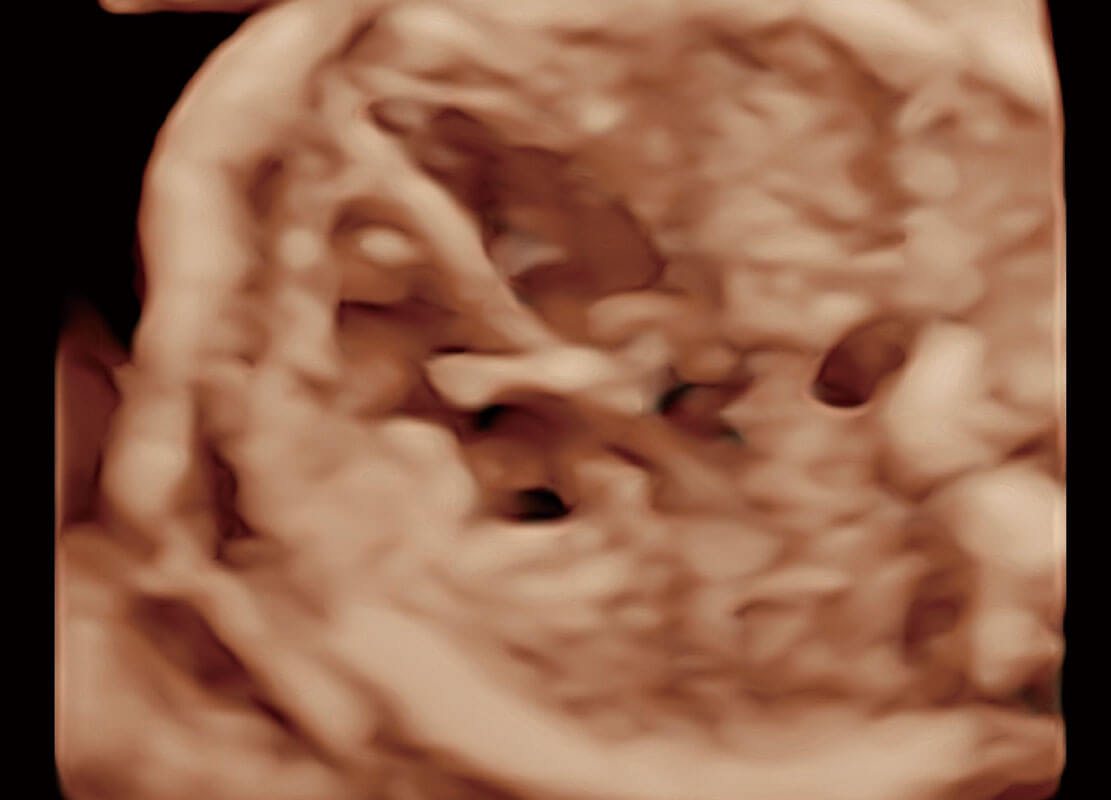

高分辨率容积成像-早孕胎儿